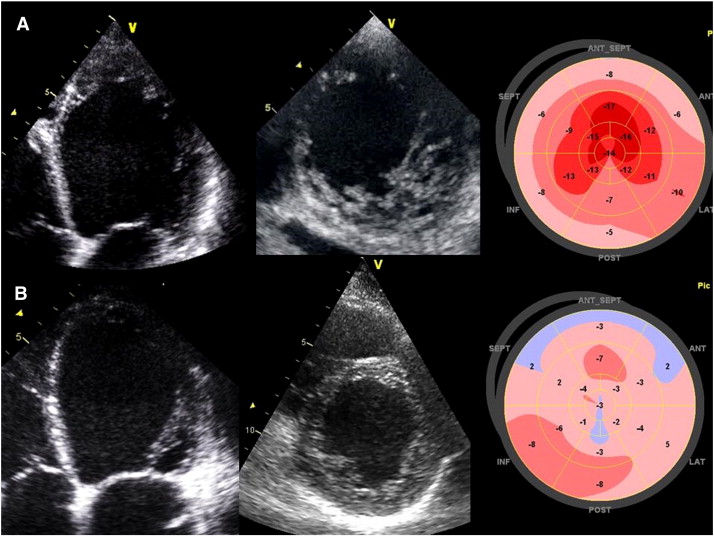

Fig. 1.

2D Myocardial deformation pattern of a dilated cardiomyopathy and a left ventricular noncompaction.

2D Transthoracic echocardiography of two patients with moderate LV systolic dysfunction (LVEF: 35%): Apical 4 chambers and parasternal short axis views and Bulls-eye of peak systolic strain values recorded from 3 apical chambers views. (A) Patient with confirmed LV non-compaction demonstrating trabeculations and deep sinusoids within non-compacted layer; higher regional peak longitudinal strain at the level of the apical non-compacted segment; lower values of systolic deformation in mid- and basal septal and inferior wall with apex/basal ratio > 1.5. (B) Dilated cardiomyopathy with overall segmental low peak longitudinal strain values.